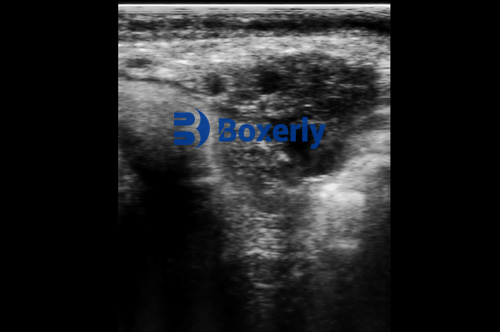

Using a farm-ready portable ultrasound scanner, vets and trained farmers can look directly into the udder tissue and milk cisterns. Unlike palpation or lab testing, this gives you real-time visual information. Here's what we can pick up on an ultrasound image:

Echogenicity of mammary tissue: Healthy udder tissue has a certain "grain" on the screen. When inflammation starts, this texture changes. Areas might appear more hyperechoic (brighter) due to fibrotic development or hypoechoic (darker) with fluid build-up.

Duct and cistern dilation: Inflammation can cause enlargement or irregular shapes in milk ducts and cisterns—visible signs that something's off.

Localized fluid or abscess pockets: These are rare in subclinical cases but might appear in cows with repeated infections that never quite clear up.